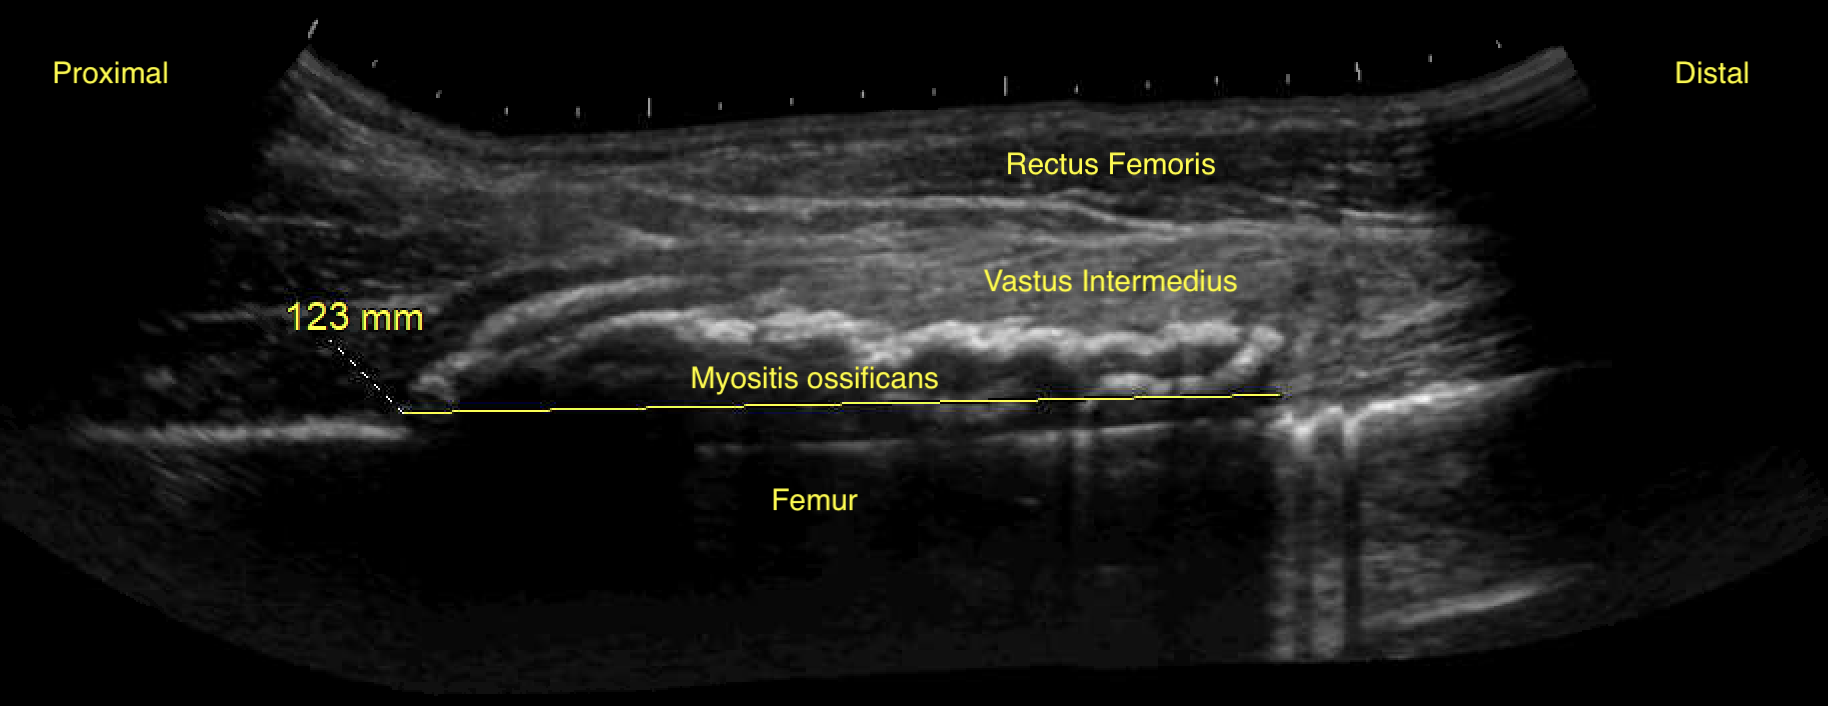

Labeled long axis view of the right quadriceps muscles with myositis ossificans four weeks after initial injury and two weeks after aspiration.